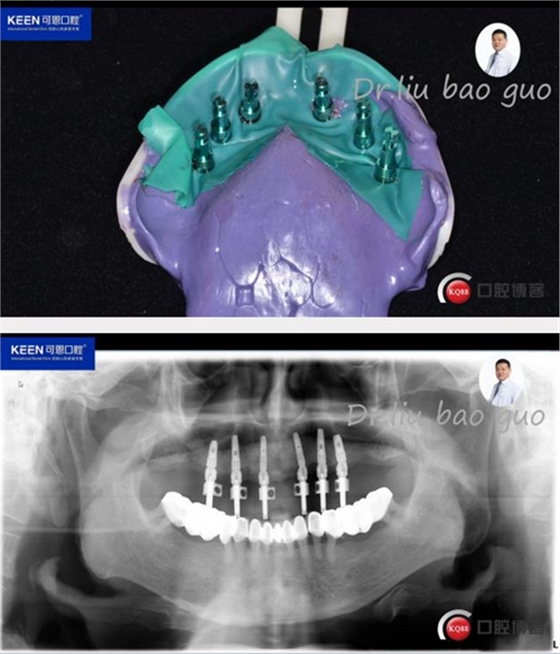

數(shù)字化種植導(dǎo)板設(shè)計(jì)及制作

種植后開始進(jìn)行取模,制作義齒